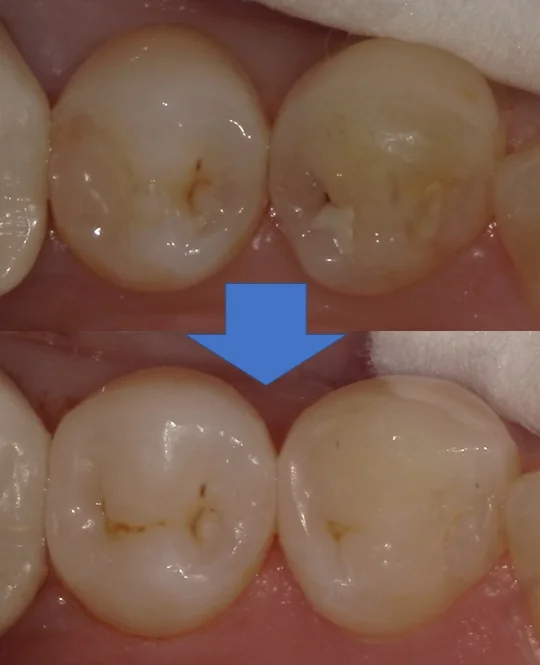

術前術後の写真がこちらです。

適合も見栄えも違和感なく綺麗に仕上げられたかと思いますヽ(゚∀゚)ノ パッ☆